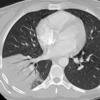

Case 14 RLL pneum CT

Date: 04/17/2005

Views: 5645